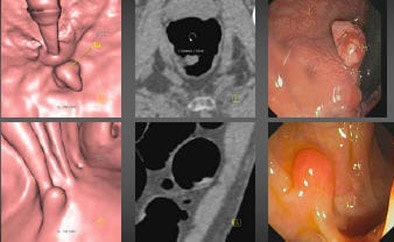

| A 67-year-old man presented with a 1.7-cm villous adenoma in the rectum and an 8-mm pedunculated polyp in the sigmoid colon at both VC (left and middle) and OC (right). FOBT was negative while FIT results were positive. |

In the per-patient analysis, "optical colonoscopy did quite a good job in all size categories, with 98%, 95%, 100% (sensitivity) for lesions smaller than 6 mm, 6 mm or larger, and 10 mm and larger," respectively, Mang said. "CT colonography was nearly in the range of optical colonoscopy in the larger size groups with 93.7% (≥ 6 mm) and 92.6% (≥ 10 mm) (sensitivity). For lesions smaller than 6 mm, VC sensitivity dropped to 76.9%." Specificity was 98.6%, 96.9%, and 61.9% for large, medium, and small polyps, respectively.

Sigmoidoscopy results were inferior to both OC and VC, yielding sensitivity of 76.9%, 64.6%, and 66.7% for small, medium, and large lesions, respectively.